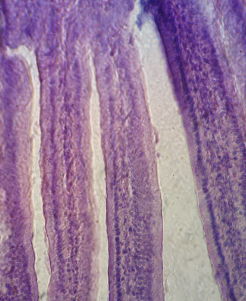

Histology of the intestinal mucosa of mice fed with hydrolyzed rice formula

The appearance of the intestinal mucosa of mice fed with hydrolyzed rice formula indicates an improvement in the structure of the intestinal mucosa compared to the positive control groups. The villi are increasingly thin and long, limited by a simple cylindrical epithelium, formed with high striated cells with regular basal nuclei that corresponds to the enterocytes (Figure 6, Figure 7).

The lamina propria appears fibrous and polymorphic with various mononuclear elements which correspond to the immune system cells (lymphocytes). The villous height indicates a highly significant difference compared with the positive control groups.

Fig. 6: Microscopic observations G (10 x 40) of intestinal biopsies of mice immunized with β-Lg then fed with hydrolyzed rice formula for 28 days.

Intestinal villi are comparable to the ones in negative control group. There is no lymphocytic infiltration.